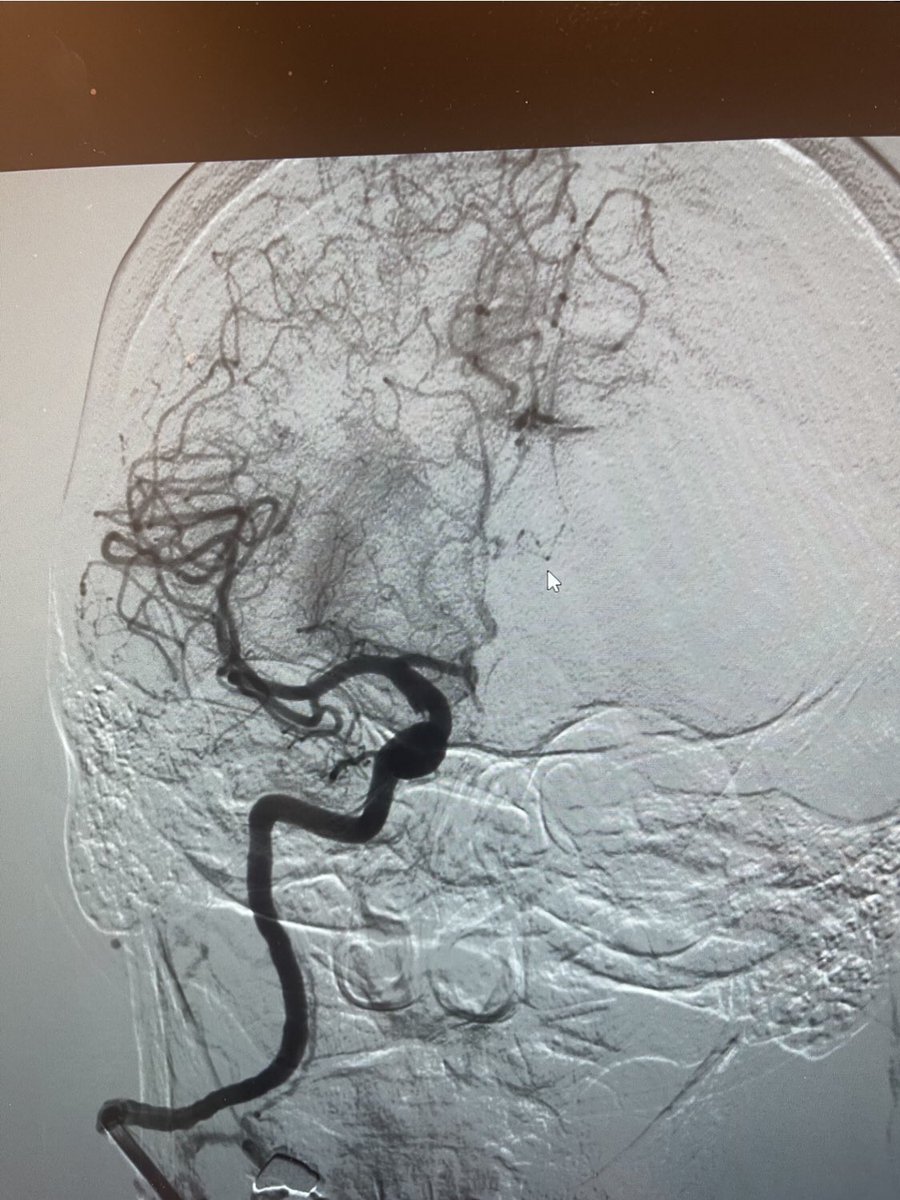

Persistent bleeding s/p FESS despite IMAX and Sphenopalatine embolization. Repeat angio shows PSA originating from a branch of the ophthalmic artery. #onyxembolization with preservation of retinal branches by paul brady and Akash Desai . Bleeding stopped, nasal packing out.